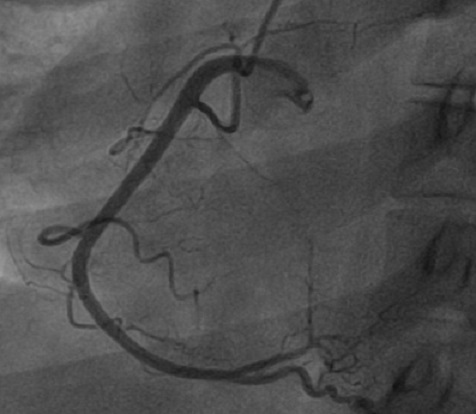

Figure 2.

Incidence OAG caudale montrant une sténose subocclusive de l'ostium du tronc commun de l'artère coronaire gauche (flèche)

A.S jeune femme de 34 ans, sans antécédents médicaux particuliers ni facteurs de risque cardiovasculaires. Admise pour des douleurs thoraciques angineuses intenses, rétrosternale constrictive, irradiant vers le membre supérieur gauche et le maxillaire inférieur, associées à des vomissements et des sueurs profuses. L'examen clinique à son admission note une patiente qui souffre au repos, ses conjonctives sont normalement colorées, tachycarde à 100bpm avec une TA à 110/75 mmhg L'examen cardiaque trouve des bruits du cœur réguliers, avec un bruit de galop gauche. Les pouls périphériques sont présents de manière bilatérale et symétrique sans souffle à l'auscultation des gros axes vasculaires accessibles. L'examen pleuropulmonaire note des crépitants des deux bases sans signes périphériques d'insuffisance cardiaque droite. Le reste de l'examen somatique est sans anomalies. L’électrocardiogramme basal de repos inscrit un RRS à 150 c/min, un sous décalage du segment ST en antérieur étendu et en inférieurs avec un sus décalage ST en AVr (Figure 1) Le bilan biologique montre des troponines I à 100 fois la normale. L’échocardiographie transthoracique de repos montre un VG dilaté, une hypocinésie globale asymétrique avec une fonction systolique ventriculaire gauche altérée (FE estimée à 25% par le Simpson biplan). Des pressions de remplissage élevées. Par ailleurs, il n'y a pas d´épanchement péricardique ni thrombus intracavitaire ni anomalies valvulaires. Le diagnostic de Syndrome coronaire aigu ST négatif à haut risque est retenu et Un traitement pharmacologique à base de Clopidogrel (Plavix*) 600 mg, Enoxaparine (Lovenox*) IV 0.5mg /kg, Aspégic 250 mg en IV, Morphine, Furosémide (Lasilix*) 40 mg est instauré aux urgences, puis adressé en unité de cardiologie interventionnelle pour coronarographie. La coronarographique montre une sténose subocclusive isolée de l'ostium du tronc commun de l'artère coronaire gauche (Figure 2). Le réseau droit est indemne de lésions (Figure 3). La patiente a bénéficié en urgence d'un pontage aorto-coronaire avec des suites post opératoire simples. L'examen anatomopathologique de la biopsie de l'artère mammaire interne montre des lésions évocatrices de la maladie de Takayasu. L'Echodoppler des troncs supra-aortiques a mis en évidence un épaississement pariétal au niveau de l'artère carotide interne droite et de la sous clavière dont le caractère est homogène et circonférentiel confirmant la maladie de Takayasu. Le patient quitte le service sous traitement médical suivant: clopidogrel (Plavix® 75 mg/j), aspirine (Kardégic® 75 mg/j), bêtabloquant (Sectral® 200 mg/j), IEC (Triatec® 5 mg/j) et rosuvastatine (Crestor® 20 mg/j), prednisone 0.5mg/kg puis adressée au service de Médecine interne pour suivi.